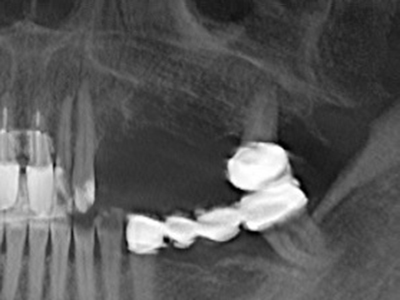

Piezosurgery has additional advantages when harvesting bone blocks. In addition to the high precision with osteotomy described above, the use of the thin saw tips specifically minimizes loss of material. Greater loss of material during harvesting can be expected with the thicker instrument tips, particularly when using Lindemann drills (Lakshmiganthan, Gokulanathan et al. 2012). The basal separation, which is necessary particularly for retromolar block transplants, is simplified by specially designed rectangular saws, with the result that piezosurgery is viewed as a precise, simple and safe procedure for harvesting retromolar bone blocks (Happe 2007) (Fig. 1-12).